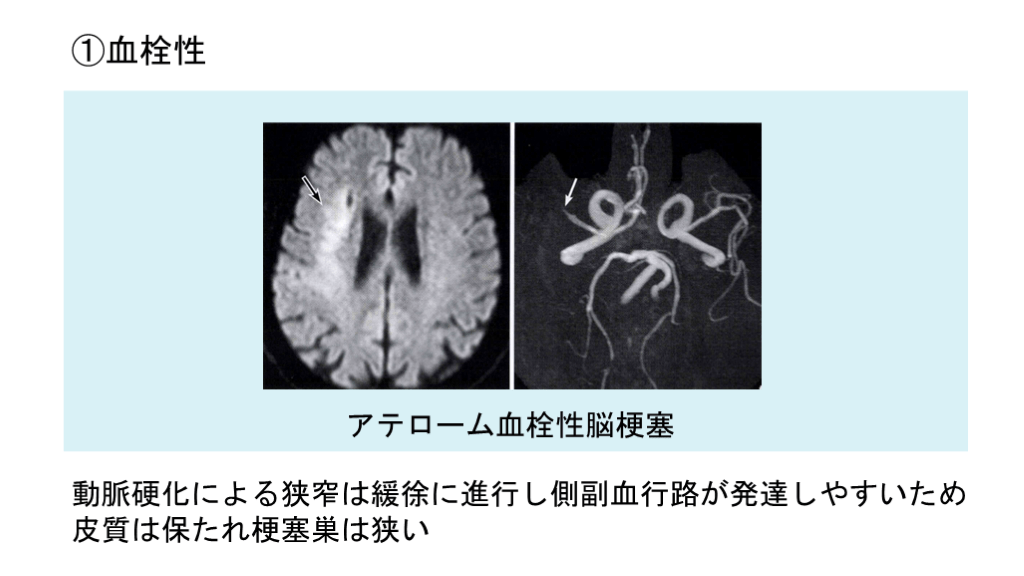

①血栓性 動脈硬化による狭窄は緩徐に進行し側副血行路が発達しやすいため皮質は保たれ梗塞巣は狭い アテローム血栓性脳梗塞

#8.